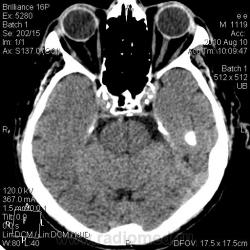

От 10.08.10 г.: В лобной доле левого полушария головного мозга кнаружи от переднего рога левого бокового желудочка гиподенсивная зона неправильной формы. В остальном картина соответствует возрасту. От 13.08.10 г.: на мой взгляд, плотность указанной зоны ещё уменьшилась и появился гиподесивный учаток в височной доле левого же полушария. Заключение: КТ-картина ишемических инфарктов в левом полушарии головного мозга различной степени давности.

Спасибо dok-a и Сергею Николаевичу за мнения. Я выставила ишемический инсульт. Первый раз, когда пациент (кстати, врач) пришел сам, была легкая оглушенность. Второй раз привезли на каталке, галлюциноз. За несколько дней консультирован и нашими, и областными неврологами. Не укладывалась клиника только в инсульт. Ликвор, взятый у нас - без особенностей. Мне показалась не совсем нормальной картина для инсульта на КТ. Но для постановки диагноза интуиции мало. Через 3 дня после поступления фербильная t. Кашель, сухие и влажные хрипы. В легких застойные дела. На КТ-контроле появилась зона ишемии в базальных отделах левой височной доли (предрекаемая неврологами по клинике и невидимая на первичной КТ). Переведен в область уже с судорогами. Через 2 недели возвращен к нам с верифицированным диагнозом ГЕРПЕТИЧЕСКОГО ЭНЦЕФАЛИТА. Учитывая редкость заболевания, выставляю здесь.